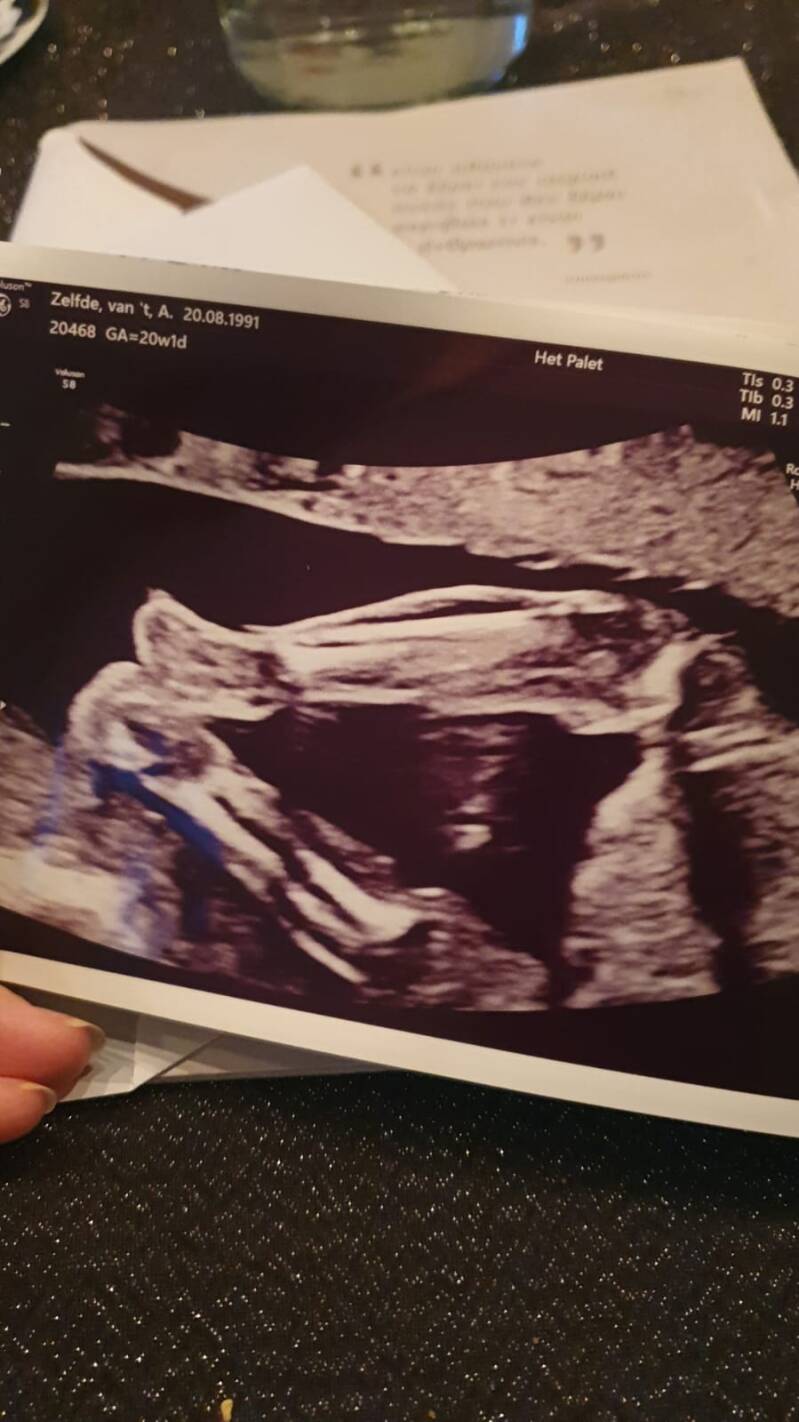

De eerste geslachtsecho liet niet goed zien wat er in de buik van Anouk verstopt zat, want er zat een beentje in de weg. "Dan moet het een meisje zijn!", riep Yvonne, ervaringsdeskundige, moeder en operatie-assistente bij o.a. de gynaecoloog. Tess begon al in haar handjes te wrijven, een nichtje! De tweede echo volgde en gaf onmiskenbaar aan wat Yvonne al wist. Maar Alex en Anouk wilden het nog voor henzelf houden. De moeder van Alex vroeg er telkens naar, wat is het nou? Om van het gezeur af te zijn, zei Alex simpelweg dat het niet te zien was.

Anouk belt met beeld, en het hoofd van Alex verschijnt op mijn telefoon. We groeten en meteen erna roept hij: "It is pink!" Na vele miskleunen in het verleden waarbij ik naïef bleef in dit soort dingen, begreep ik dit keer direct wat hij bedoelde. Er is een meisje op komst! Het was niet langer binnen te houden, de vreugde was te groot. Zijn wens, en die van Tess, gaan in vervulling. Maar goed dat we er geen geld op hadden ingezet, want dan was de spoeling dun geweest, want iedereen had ingezet op een meisje, behalve Max en Stan. Daan was het waarschijnlijk om het even, een jongen of een meisje, allemaal even niks aan voorlopig. Maar Tess ziet het helemaal zitten, een nichtje om over te moederen, om haar speelgoed mee te delen, om haar haartjes te kammen, haar nageltjes te lakken, mooie kleertjes aan te trekken, haar Frozenjurk bijvoorbeeld. Ze mag in haar poppenwagen liggen en al haar knuffels hebben.